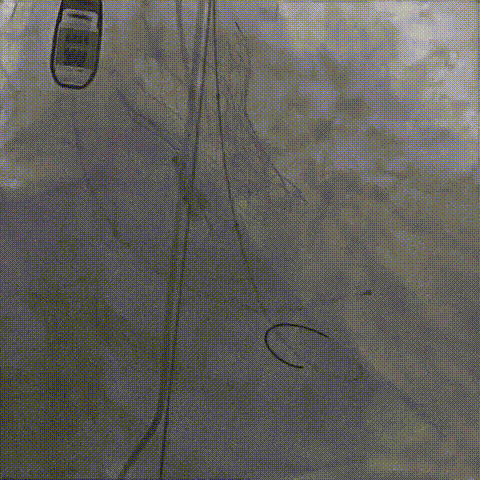

初次释放,无冠窦畸形猪尾难以到达窦底,定位带来挑战;释放至工作位,瓣膜(AV29)位置偏低

瓣膜(AV29)完全回收后重新定位释放